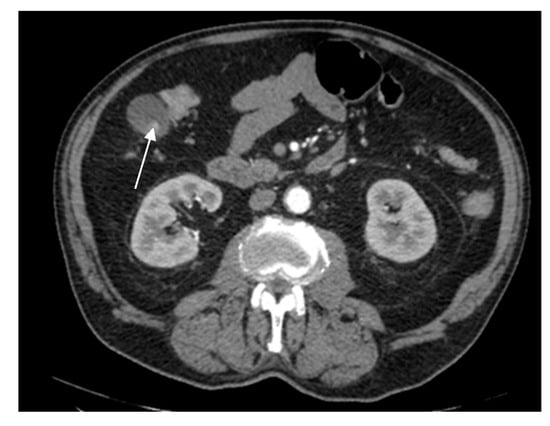

A 69-year-old female patient with a past medical history of diabetes type II presented to the Emergency Department with a 2-day upper abdominal pain, accompanied by hypotension and oligoanuria. Routine laboratory evaluation showed elevated inflammatory markers (leukocytosis, procalcitonin 100 ng/mL, CRP 126 mg/L), elevated transaminases and ferritin. The patient underwent contrast-enhanced computed tomography (Figure 6). CT images depicted a distended gallbladder (99 mm in longitudinal measurement), with asymmetrical thick-walled gallbladder (16 mm), heterogeneous contrast enhancement (Panel A), with a gallbladder neck stone (10 mm), extended to the duodenum (Panel B and Panel C). CT showed multiple low-attenuation hepatic masses with peripheral enhancement, adjacent to the gallbladder fossa (segment V) and intrahepatic biliary tract dilatation. Below the liver and adjacent to the gallbladder fundus, fat standing and free fluid were observed. These imaging findings were suggestive of acute cholecystitis complicated by an intrahepatic abscess or gallbladder carcinoma with wall perforation into the adjacent liver.

Figure 6. Multiplanar sections of contrast-enhanced CT acquisitions richly illustrating gallbladder carcinoma with an associated necrotizing infectious component. (A,B). Distended gallbladder with asymmetrical thick-walled gallbladder (16 mm) (white arrow). (C,D). Abscess adjacent to the gallbladder (black arrow); extension to the duodenum (blue arrow).